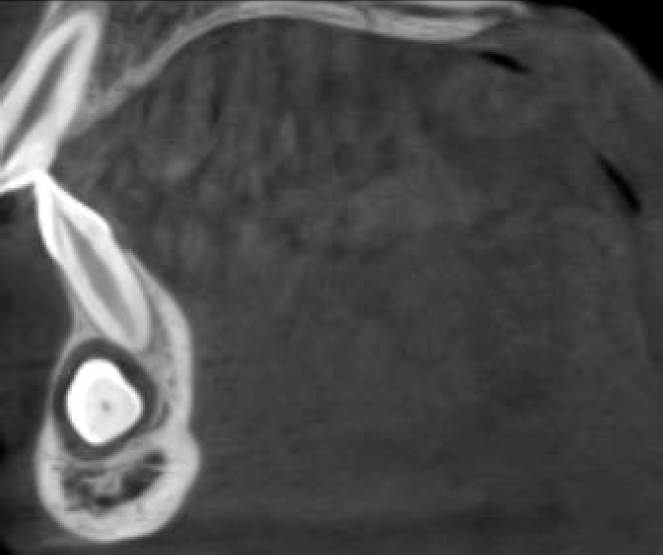

La posición radicular está al centro del reborde y la zona vestibular de la corona en relación a los OD 3.1 y 3.2. No se observan imágenes sugerentes de reabsorción radicular anómala a nivel de incisivos inferiores (Figura 3). Se observa que el canino ya cruzó más allá de la línea media y se encuentra en una etapa de desarrollo muy avanzada con la formación de la raíz casi completa. Por lo anterior, las posibilidades de realizar un tratamiento de ortodoncia exitoso y posicionar la pieza en una posición correcta son casi inexistentes, por lo que el tratamiento a seguir fue la extracción dentaria, descartando el trasplante por ausencia del espacio interdentario necesario.

Figura 3 Tomografía computarizada Cone-Beam, año 2015. Relación de la porción coronaria de la pieza 4.3 hacia vesti bular del ápice del órgano dental 3.1 y 3.2. El saco pericoronario se encuentra levemente ensanchado y se observa un marcado adelgazamiento de la tabla ósea vestibular. No se observa reabsorción de las raíces de los dientes adyacentes.